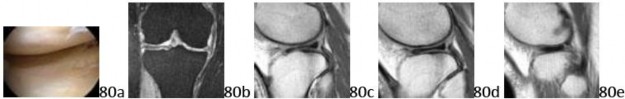

52a 52b 52c Figures 52a through 52c show the axial, coronal, and sagittal T2-weighted MRI scans respectively of a knee. The highlighted structure represents what anatomic finding?

5. # Transverse meniscal ligament

DISCUSSION: The images show a transverse meniscal ligament, which connects the anterior horns of the medial and lateral menisci. On sagittal images, the interface of this structure with the anterior horn of the lateral meniscus often simulates a tear. Following this structure over several successive images is helpful in identifying it as a normal structure. There is no abnormal signal within the menisci to suggest a tear. A meniscofemoral ligament is a posterior structure. A ligamentum mucosum or infrapatellar plica is best seen on the sagittal image and runs from the intercondylar notch to the anterior fat pad. The Preferred Response to Question # 52 is 5.